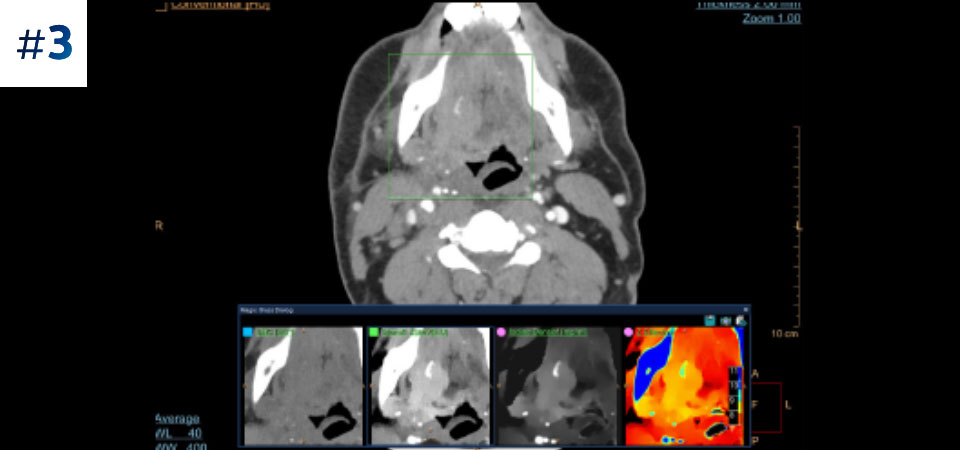

See the difference between spectral-detector CT and conventional CT

Learn about the advantages of spectral-detector CT